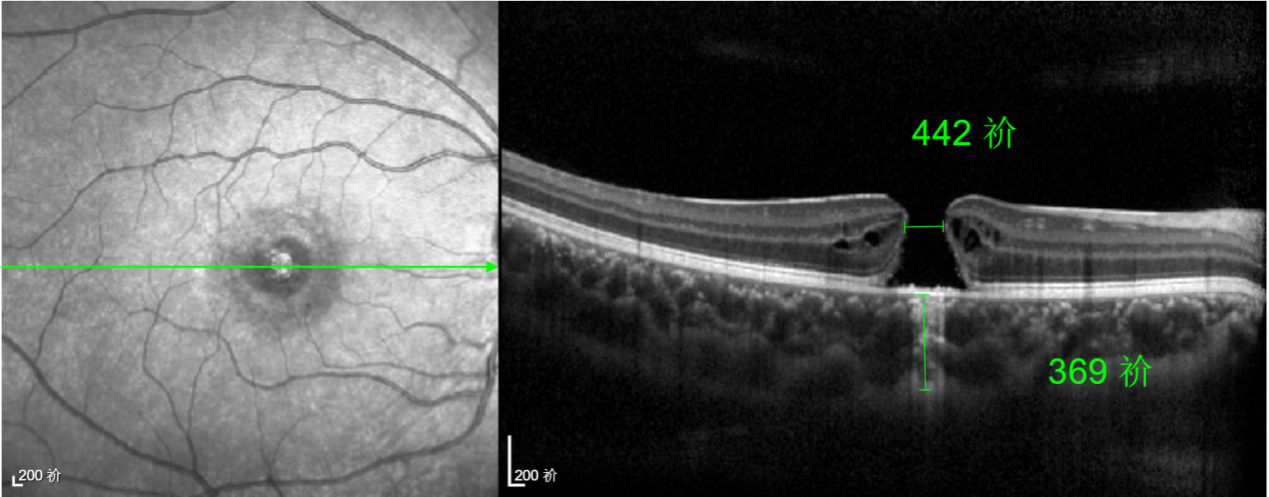

由于裂孔較小,當(dāng)?shù)蒯t(yī)院建議先觀察,看看裂孔是否能夠自愈。可半年時(shí)間過去了,誠誠傷眼的裂孔不僅沒有愈合的跡象,反而越來越大,這讓家長的心揪得更緊了。

經(jīng)過詳細(xì)的檢查和評(píng)估,王曉波主任決定采用“內(nèi)界膜翻轉(zhuǎn)覆蓋聯(lián)合粘彈劑固定術(shù)”為誠誠進(jìn)行治療。

除此之外,利用自體組織覆蓋為黃斑裂孔提供了理想的愈合環(huán)境,裂孔閉合速度顯著快于傳統(tǒng)方法。誠誠接受手術(shù)24小時(shí)后,檢查可見內(nèi)界膜瓣位置良好;術(shù)后1個(gè)月,黃斑裂孔已經(jīng)閉合,視力恢復(fù)到0.5;術(shù)后兩個(gè)月,視力進(jìn)一步提升到0.7。